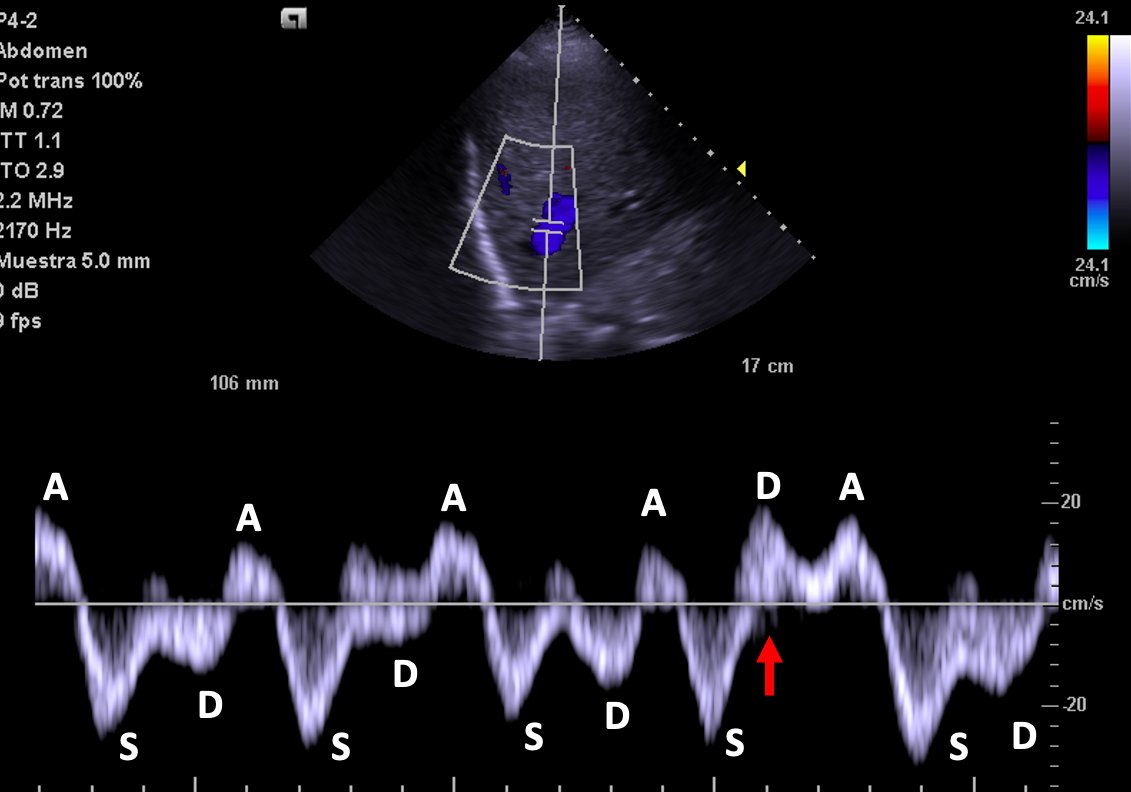

Hepatic Vein Doppler shows characteristic D wave reversal!

Again: This is strongly suggestive of Tamponade!!🚨

Hepatic vein shows no D wave reversal